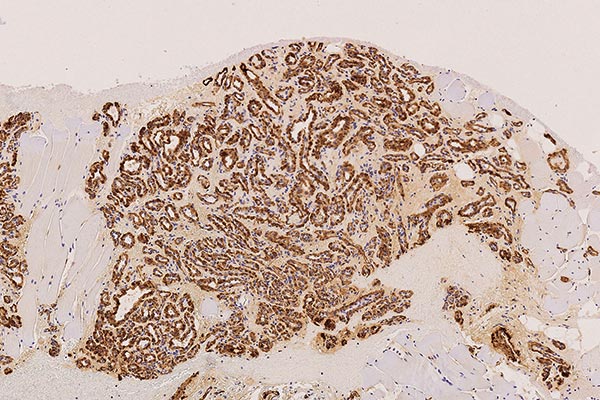

In der 130-fachen Vergrößerung (immunhistochemische CD31-Färbung zur Darstellung von Gefäßendothelien) zeigt sich eine intensive braune Anfärbung der endothelialen Strukturen. Dies beweist den Gefäßcharakter der Läsion. Die Gefäße sind beim infantilen Hämangiom als vaskulärer Tumor typisch lobuliert angeordnet.

In der 130-fachen Vergrößerung (WT1-Färbung) spricht auch die zytoplasmatische Positivität (braune Anfärbung im Bereich der Endothelzellschicht) gegen eine vaskuläre Malformation und für einen vaskulären Tumor, also hier passend zu einem infantilen Hämangiom.

In der 250-fachen Ausschnittsvergrößerung der GLUT1-Färbung zeigen die Kapillaren des infantilen Hämangioms eine charakteristische immunhistochemische GLUT1-Expression (braune Färbung der Endothelzellschicht), die normalerweise lediglich in plazentaren Kapillaren und von diesen abgeleiteten vaskulären Tumoren eine Positivität zeigt. Daher auch die Annahme, dass sich infantile Hämangiome aus vaskulären Präkursorzellen der Plazenta ableiten. In anderen Hämangiomen (z. B. angeborenen Hämangiomen wie NICH oder RICH) ist GLUT1-negativ. Dies stellt das wichtigste differentialdiagnostische histologische Kriterium zum infantilen Hämangiom dar. Die in den Lumina enthaltenen Erythrozyten zeigen ebenfalls eine GLUT1-Positivität und dienen damit als positive interne Kontrolle, dass die Färbung technisch gut funktioniert hat.

Die histopathologische Aufarbeitung zeigte dann den typischen Befund eines benignen vaskulären Tumors. Die Läsion war von vielen lobulären, kapillären Infiltraten durchsetzt, mit symmetrischer Gefäßwand/Perimyozytenschicht (SMA). Die CD31- und die WT1-Positivität legten ebenfalls einen vaskulären Tumor nahe. Die sichere Differentialdiagnose gelingt dann mit der GLUT1-Färbung, die beim infantilen Hämangiom als einzigem vaskulären Tumor endothelial positiv ist, wie in diesem Fall. Als Ausdruck des Wiedereinsetzens einer Proliferationsaktivität mit Wiedervergrößerung von Teilen des Tumors findet sich in bis zu 10 % der Endothelzellen eine Ki67-Anfärbung.